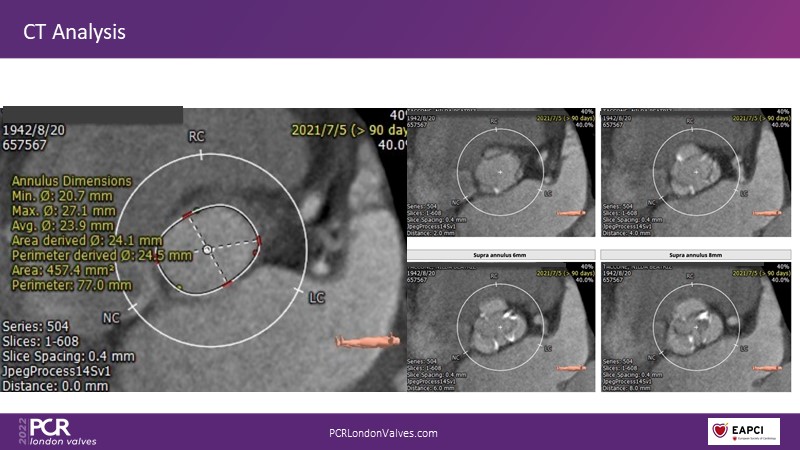

In this session, a panel of experts introduce the VitaFlow TAVI system, a good option for patients with complex anatomies. They also present the five-year results of VitaFlow in severe aortic stenosis.

- To learn about the VitaFlow TAVI system and the five-year results of VitaFlow in severe aortic stenosis